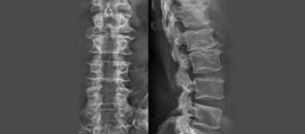

허리통증 원인을 찾기 위해서는 기본적으로 X레이 촬영을 해야합니다.

추간판 사이의 간격이라든지 허리가 휘어져 있는 밸런스를 확인하며 골절 또는 척추에 균이 감염되지 않았는지 확인하여 허리통증 원인을 진단합니다.

근육세포가 긴장을 하거나 살짝 다친 경우를 염좌라고하며, 골절이 생겼거나 디스크가 다치거나 튀어나온 경우는 mri 검사를 통해 추간판탈출증으로 진단하게 됩니다.